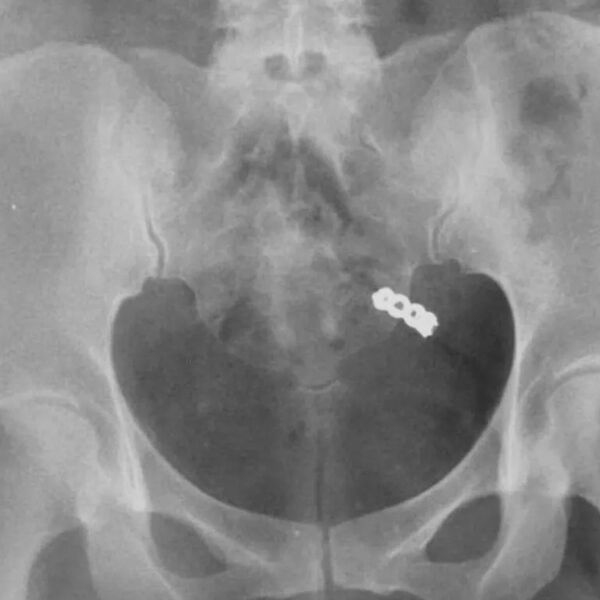

После тщательных поисков в гостиничном номере, Данна решила сделать рентген. Снимок показал, что кольцо действительно было внутри женщины. Врачи заверили ее, что переживать не нужно — украшение выйдет их организма естественным образом, что и произошло на следующий день.